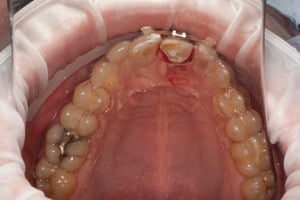

Przykład ekstruzji ortodontycznej za pomocą płytki termoformowalnej i zameczka ortodontycznego: